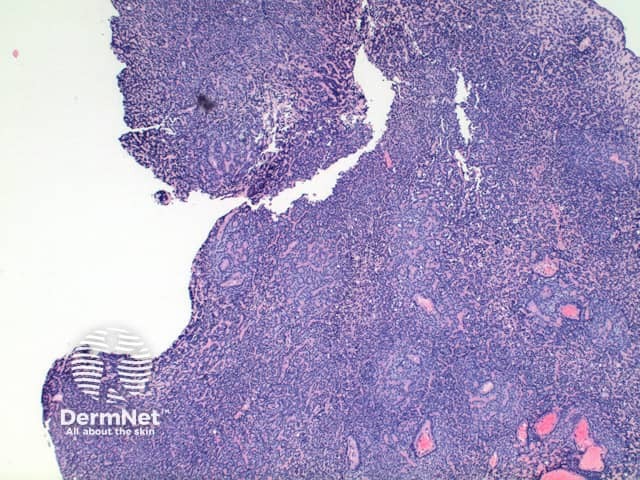

Low power view of eccrine spiradenoma shows a well-circumscribed tumour nodule arising within the dermis or superficial subcutis. The tumour is comprised of a diffuse dense basophilic cellular proliferation (Figures 1 and 2). In some cases a prominent vascular component can be seen (Figures 2 and 3). Eosinophilic hyaline deposits are seen in amongst the tumour cells as droplets and bands (Figure 4). A lymphocytic infiltrate is seen and when heavy can mimic lymphoid tissue.

Figure 1